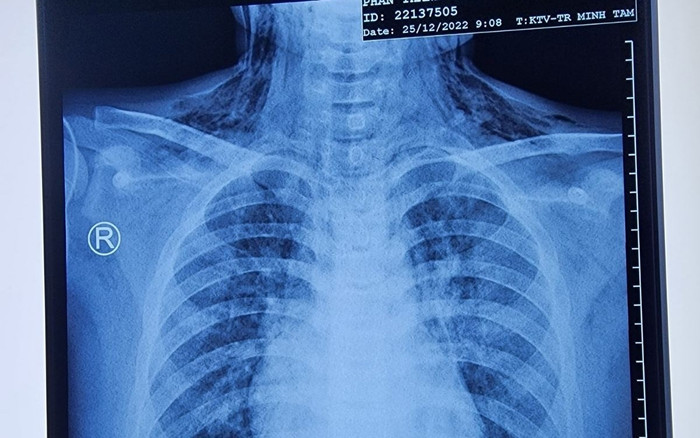

Nghi ngờ hóc dị vật đường thở, ê-kíp bác sĩ đã nội soi phát hiện dị vật nằm bít lòng phế quản trung gian phổi. Cụ thể, dị vật này là đậu nhựa bút bi đang nham nhở xước bởi các chất tiết đàm nhớt.